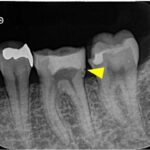

左上の第一小臼歯(4番)には虫歯が認められ、レントゲン・CTにて明瞭な骨吸収像が認められました。痛みなどの症状はないものの、このまま被せ物の治療をやりかえる場合、将来的に根の先の膿が大きくなる可能性があるため、根管治療が第一選択であるとお伝えし、根管治療を開始することになりました。

治療後6ヶ月で根尖部の透過像は縮小傾向を認め経過良好のため、ジルコニアクラウンによる最終補綴治療へ移行しました。